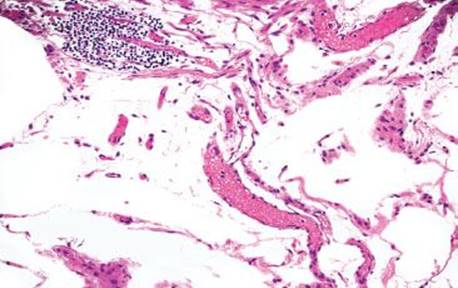

Figure 4.247 Air artifact. Higher power shows the air pockets are pushing apart the normal cellular constituents (note the lymphoid aggregate in the upper left, vessels in the middle, and ganglion cells in the upper right). In addition, the air pockets have no endothelial lining (to suggest a lymphovascular space) or nuclei (to suggest an adipocyte), both helpful clues to the diagnosis of air artifact. Also, note there is no tissue response (there are no foreign body giant cells reacting to the displaced gas). This emergent bowel resection occurred almost immediately after the perforation, before the tissue had sufficient time to react to the infiltrating gas.

Figure 4.248 Air artifact. An alternative field shows large, bizarre air pockets (asterisks), which dissect the resident tissue. Lipomas do not tend to percolate around native structures such as ganglion cell clusters, nerves, fibrous tissue, and blood vessels, as seen in this example of an air artifact. Also, there is no epithelial lining and no nuclei to suggest a lymphovascular space or adipocytic lesion, respectively.